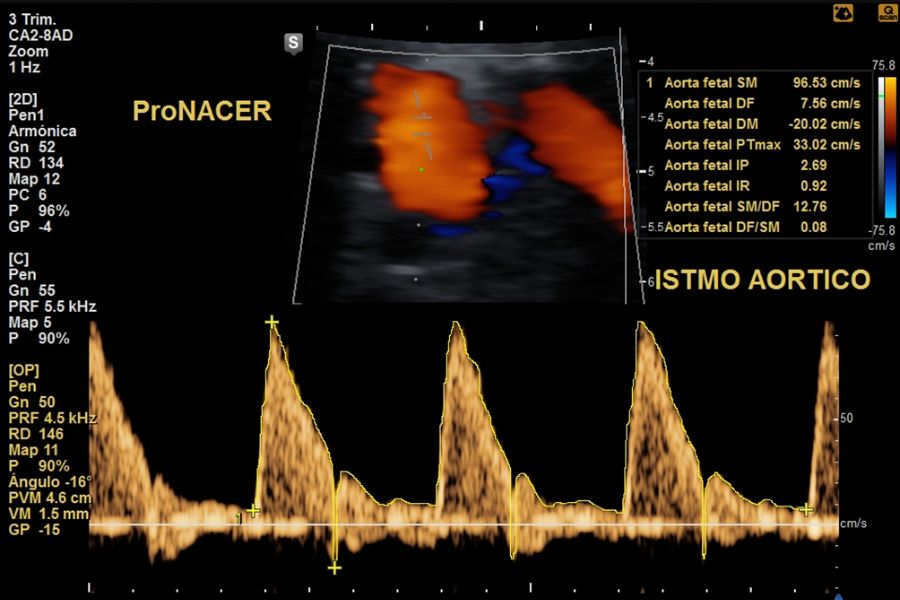

Doppler fetoplacentario